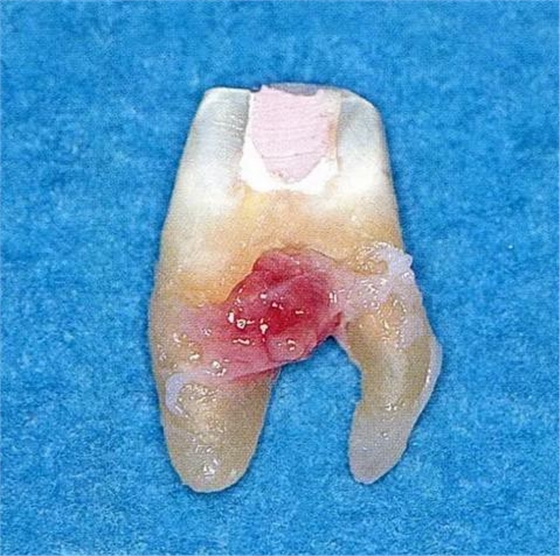

▼圖6-2中下頜第一后磨牙雖然切除了一半,但是遠(yuǎn)中根也有2根分根,所以不得已拔除(被拔除遠(yuǎn)中根的近中面觀察)。

[多根分叉]

▼圖6-3上頜第一后磨牙的牙根形態(tài)異常。舌側(cè)面觀察。